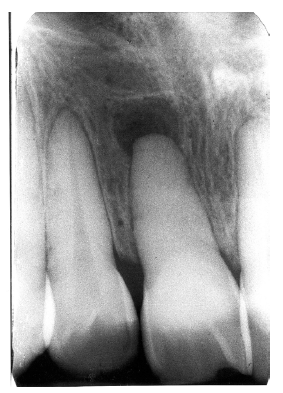

Invagination (Dens in Dente)

Invagination represents a deep infolding of the tooth with extension of the enamel down through the dentin into the pulp. Such teeth can be severely deformed, appearing with an enlarged pulp chamber that has been likened to a tooth within a tooth (dens in dente).

The most commonly affected tooth is the permanent maxillary lateral incisor (Figure 34 and Figure 35). Single dens in dente are most common, but double varieties also occur.

Figure 34 - Invagination

Figure 34